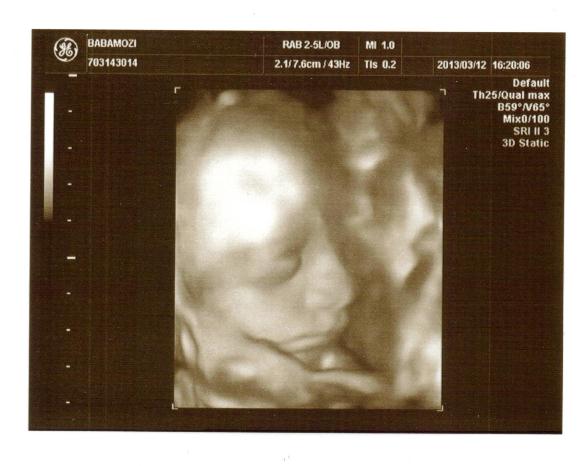

Íme a képek a babócámról:

Ásítás közben

Ásítás közben Üdv mindenkinek!